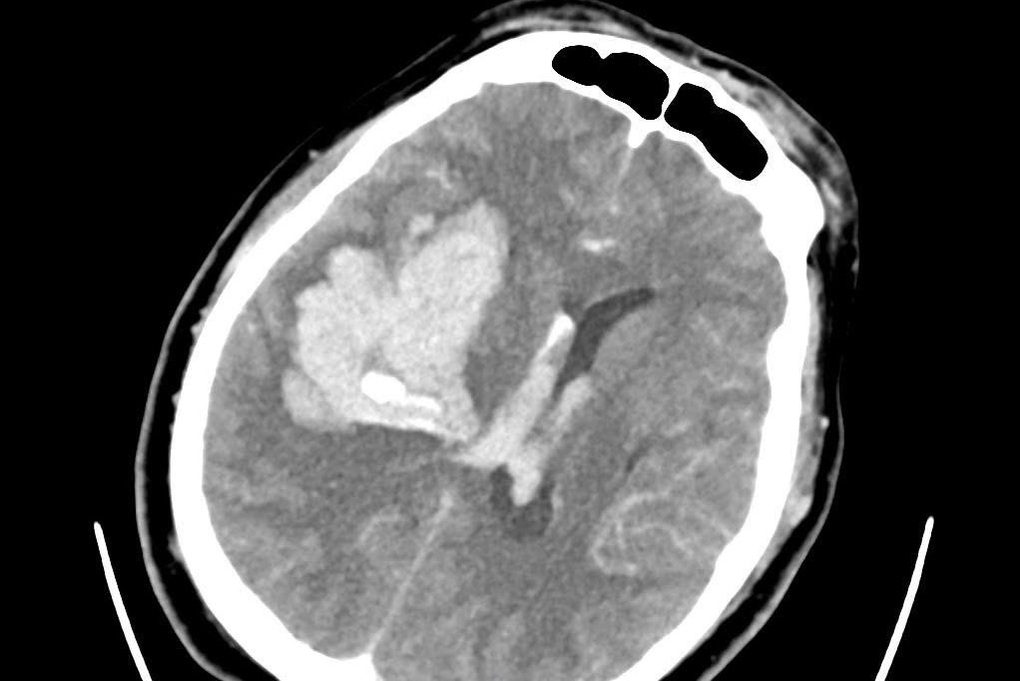

Tại đây, ảnh chụp CT não cho thấy bệnh nhân bị xuất huyết não lớn, được đặt nội khí quản để bảo vệ đường thở và chuyển mổ cấp cứu.

Sau khi tổng hợp tất cả dữ liệu, nam bệnh nhân được chẩn đoán xuất huyết nội sọ, trên nền bệnh lý tăng huyết áp, hen suyễn. Người đàn ông được tiến hành phẫu thuật sọ não để xử lý tình trạng xuất huyết, hiện tại được điều trị, theo dõi sát tại khoa Hồi sức tích cực (ICU).

Ảnh chụp CT cho thấy bệnh nhân bị xuất huyết não nặng (Ảnh: BS).